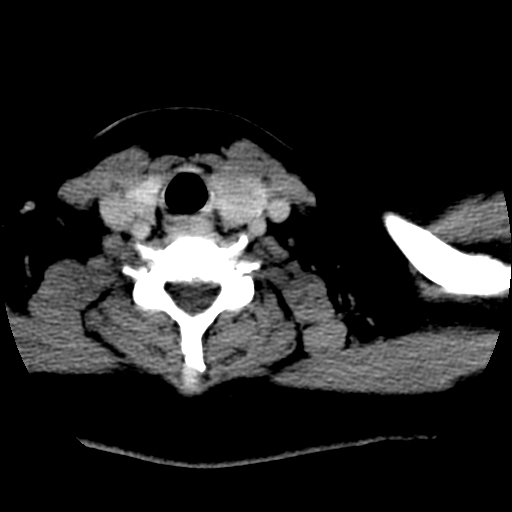

标题: CT25491:女,55岁,发现左侧甲状腺肿块一个月。 [打印本页]

女,55岁,发现左侧甲状腺肿块一个月,彩超示:甲状腺多发结节伴左叶结节液化。

边界清,无明显强化,考虑考虑甲状腺腺瘤

考虑左侧甲状腺结节性甲状腺肿,不排除甲状腺腺瘤。